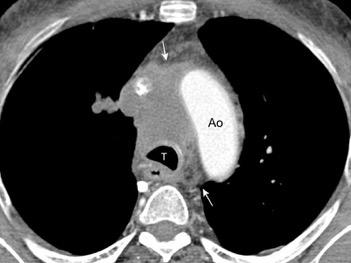

85. ENSANCHAMIENTO MEDIASTÍNICO AGUDO

102. HEMATOMA MEDIASTÍNICO.

Hematoma intramural

Disección aórtica

Rotura de aneurisma aórtico

Mediastinitis aguda